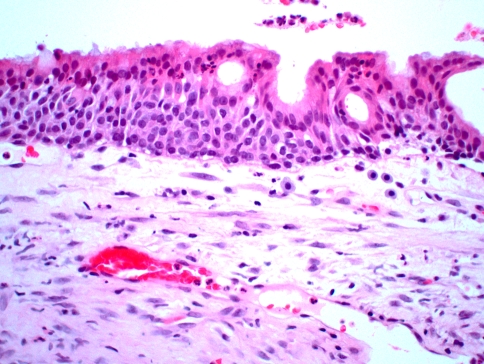

Microscopic examination reveals a basic lining of stratified squamous epithelium that is variable in thickness. However, the superficial cells tend to be cuboidal to columnar in shape, often with an irregular, papillary surface. Within the epithelium are occasional gland-like spaces that are lined by similar cuboidal/columnar cells (Fig 6). Mucin-producing cells and cilia sometimes can be identified. Pools of mucicarminophilic material can be found within the gland-like spaces. Some areas of the lining may form spherical aggregates of swirling epithelial cells reminiscent of the pattern observed in the lateral periodontal cyst. This finding lends support for an odontogenic origin of this lesion, and also suggests a similar histogenesis.

Fig. 6.

Glandular odontogenic cyst. This medium-high power photomicrograph shows a cyst lined by stratified squamous epithelium with a surface layer of eosinophilic columnar cells. Note the intraepithelial gland-like spaces, which are also lined by these cuboidal/columnar cells